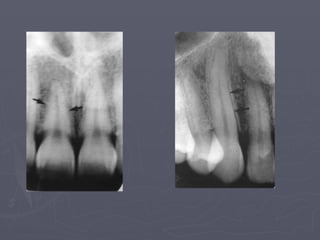

Nutrient canals :

The arrows above

identify nutrient

Canals.

They are most often seen

in

Persons with thin bone

and in

Those with high blood

pressure

Or advanced

periodontitis.

Nutrient canals

Nutrient canals : Thearrows above identify nutrient Canals. They are most often seen in Persons with thin bone and in Those with high blood pressure Or advanced periodontitis. Nutrient canals